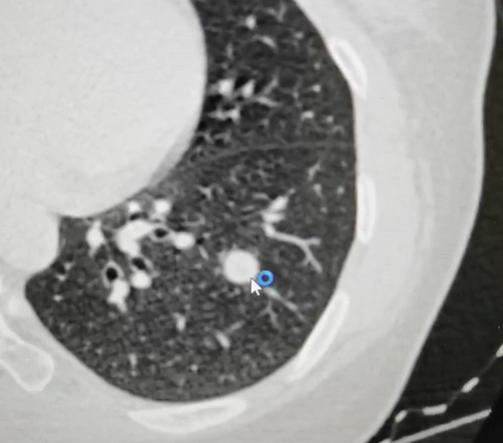

很多朋友一拿到影像检查报告,看到写着“占位性病变”这几个字,心里就咯噔一下,忍不住往坏处想:“我是不是得了癌症”? 其实啊,肺部发现占位,真不一定就是肿瘤!引起占位的原因有很多,其中最常见的是炎症,比如肺炎好了之后局部留下的高密度影。 除此之外,结核、真菌感染等也可能在肺里形成占位。 一般来说,肺部的占位分为良性和恶性两大类。良性占位包括肺炎、肺结核、肺囊肿、错构瘤,还有真菌感染等等; 而恶性占位,就是大家比较担心的肺癌、肺淋巴瘤、肺肉瘤,或者从别处转移过来的肿瘤等等。 医生在判断这个占位是良性还是恶性的时候,会仔细看它的“长相”。比如,如果影子看起来像一片云雾,边界模糊,很多时候是炎症;如果形态圆溜溜的,边缘光滑,甚至有点钙化,那多数是良性的。 但如果这个占位长得不太规则,表面有分叶,或者伴有“气道征”等变化,医生就会警惕起来,考虑是不是恶性肿瘤,比如肺癌。 总之,发现报告上有“占位”先别慌,大多数情况还是良性的。关键是把报告交给专业医生,让他们结合你的具体情况来做分析和判断。[玫瑰][谢谢]